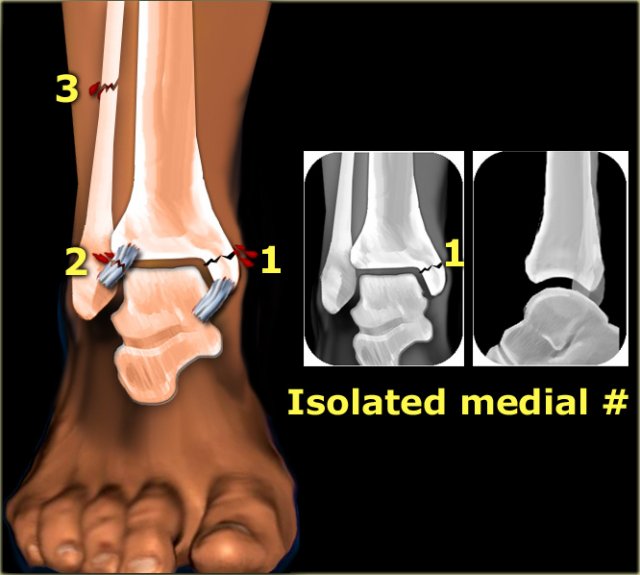

1. Isolated fracture of the medial malleolus

Isolated fracture of the medial malleolus

According to Lauge-Hansen this is the first stage of a pronation exorotation injury, which results in a Weber C fracture.

So we have to look for higher stages.

The injury can continue to the following:

• stage 2: rupture of the anterior syndesmosis

• stage 3: high fibular fracture

• stage 4: rupture of the posterior syndesmosis

In all these subsequent stages, purely ligamentous injury will not be visible on the radiographs of the ankle.

So even in a Weber C stage 4 sometimes only a fracture of the medial malleolus will be visible.

In the illustration we see the fractures and ligamentous injury on the left and the resulting x-rays on the right.